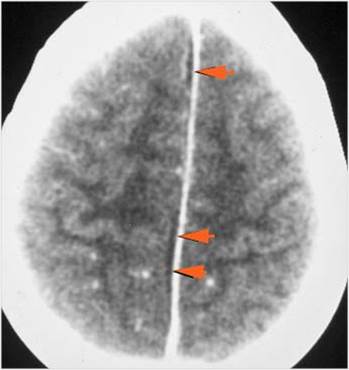

There is evidence of thrombus, thrombophlebitis or other occlusive or inflammatory process of the cortical veins, sphenoparietal sinus or sagittal sinus. [Yes/No]

There is brain edema specifically involving the frontal and temporal lobes. [Yes/No]

There is cerebritis specifically involving the frontal and temporal lobes. [Yes/No]

There is brain abscess specifically involving the frontal and temporal lobes. [Yes/No]